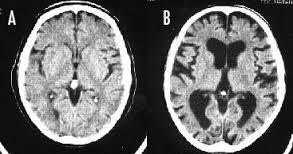

喫煙をすると頭が悪くなるのは本当です。 長期の喫煙により大脳皮質が薄くなり、認知機能が低下してしまうのです。 ※画像左(A)は正常の脳、右(B)は喫煙者の脳です。 左の脳と比べて、右の脳は萎縮し隙間だらけになっています。 喫煙をやめても元の状態に回復するまで数十年かかるそうです。

--- 「喫煙者の脳」やはり異変が起きていた(石田雅彦) - Yahoo!ニュース ---

タバコを吸うと脳がすっきりするのは真っ赤な嘘だ。研究によれば喫煙者の脳では明らかに異常が起きている。認知機能も低下し、大脳皮質が元に戻るのには25年もかかる。一刻も早くタバコなど止めたほうがいい。